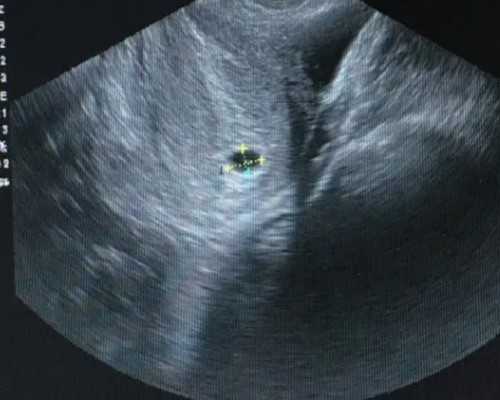

第三个是AFC,就是基础卵泡。是在月经第2~5天,经阴道B超检查双侧卵巢内的小于8mm的小卵泡个数,这些卵泡是卵巢内功能性生长卵泡,数目多提示卵巢储备功能好,卵泡生长发育是看的见的,正常的个数应该在8~10个。